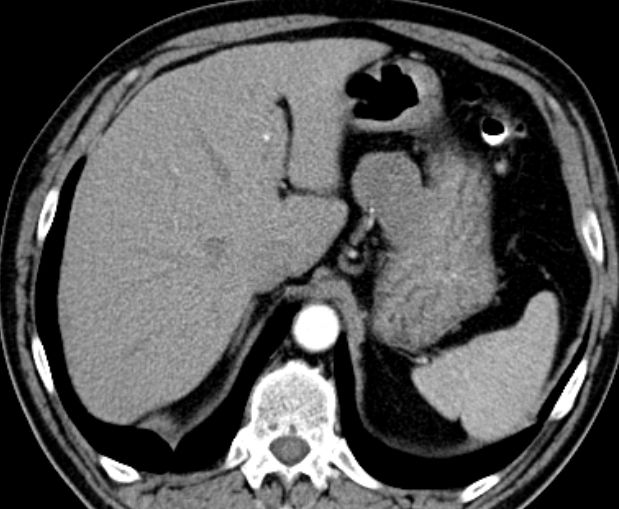

56-jähriger Mann mit großer Raumforderung der Magenvorderwand.

Gallenblase und Leber werden etwas verdrängend.

Vergrößerte Lymphknoten sind nicht nachweisbar.![]() | |||||||||||||||||||||||||||||||||||||||||